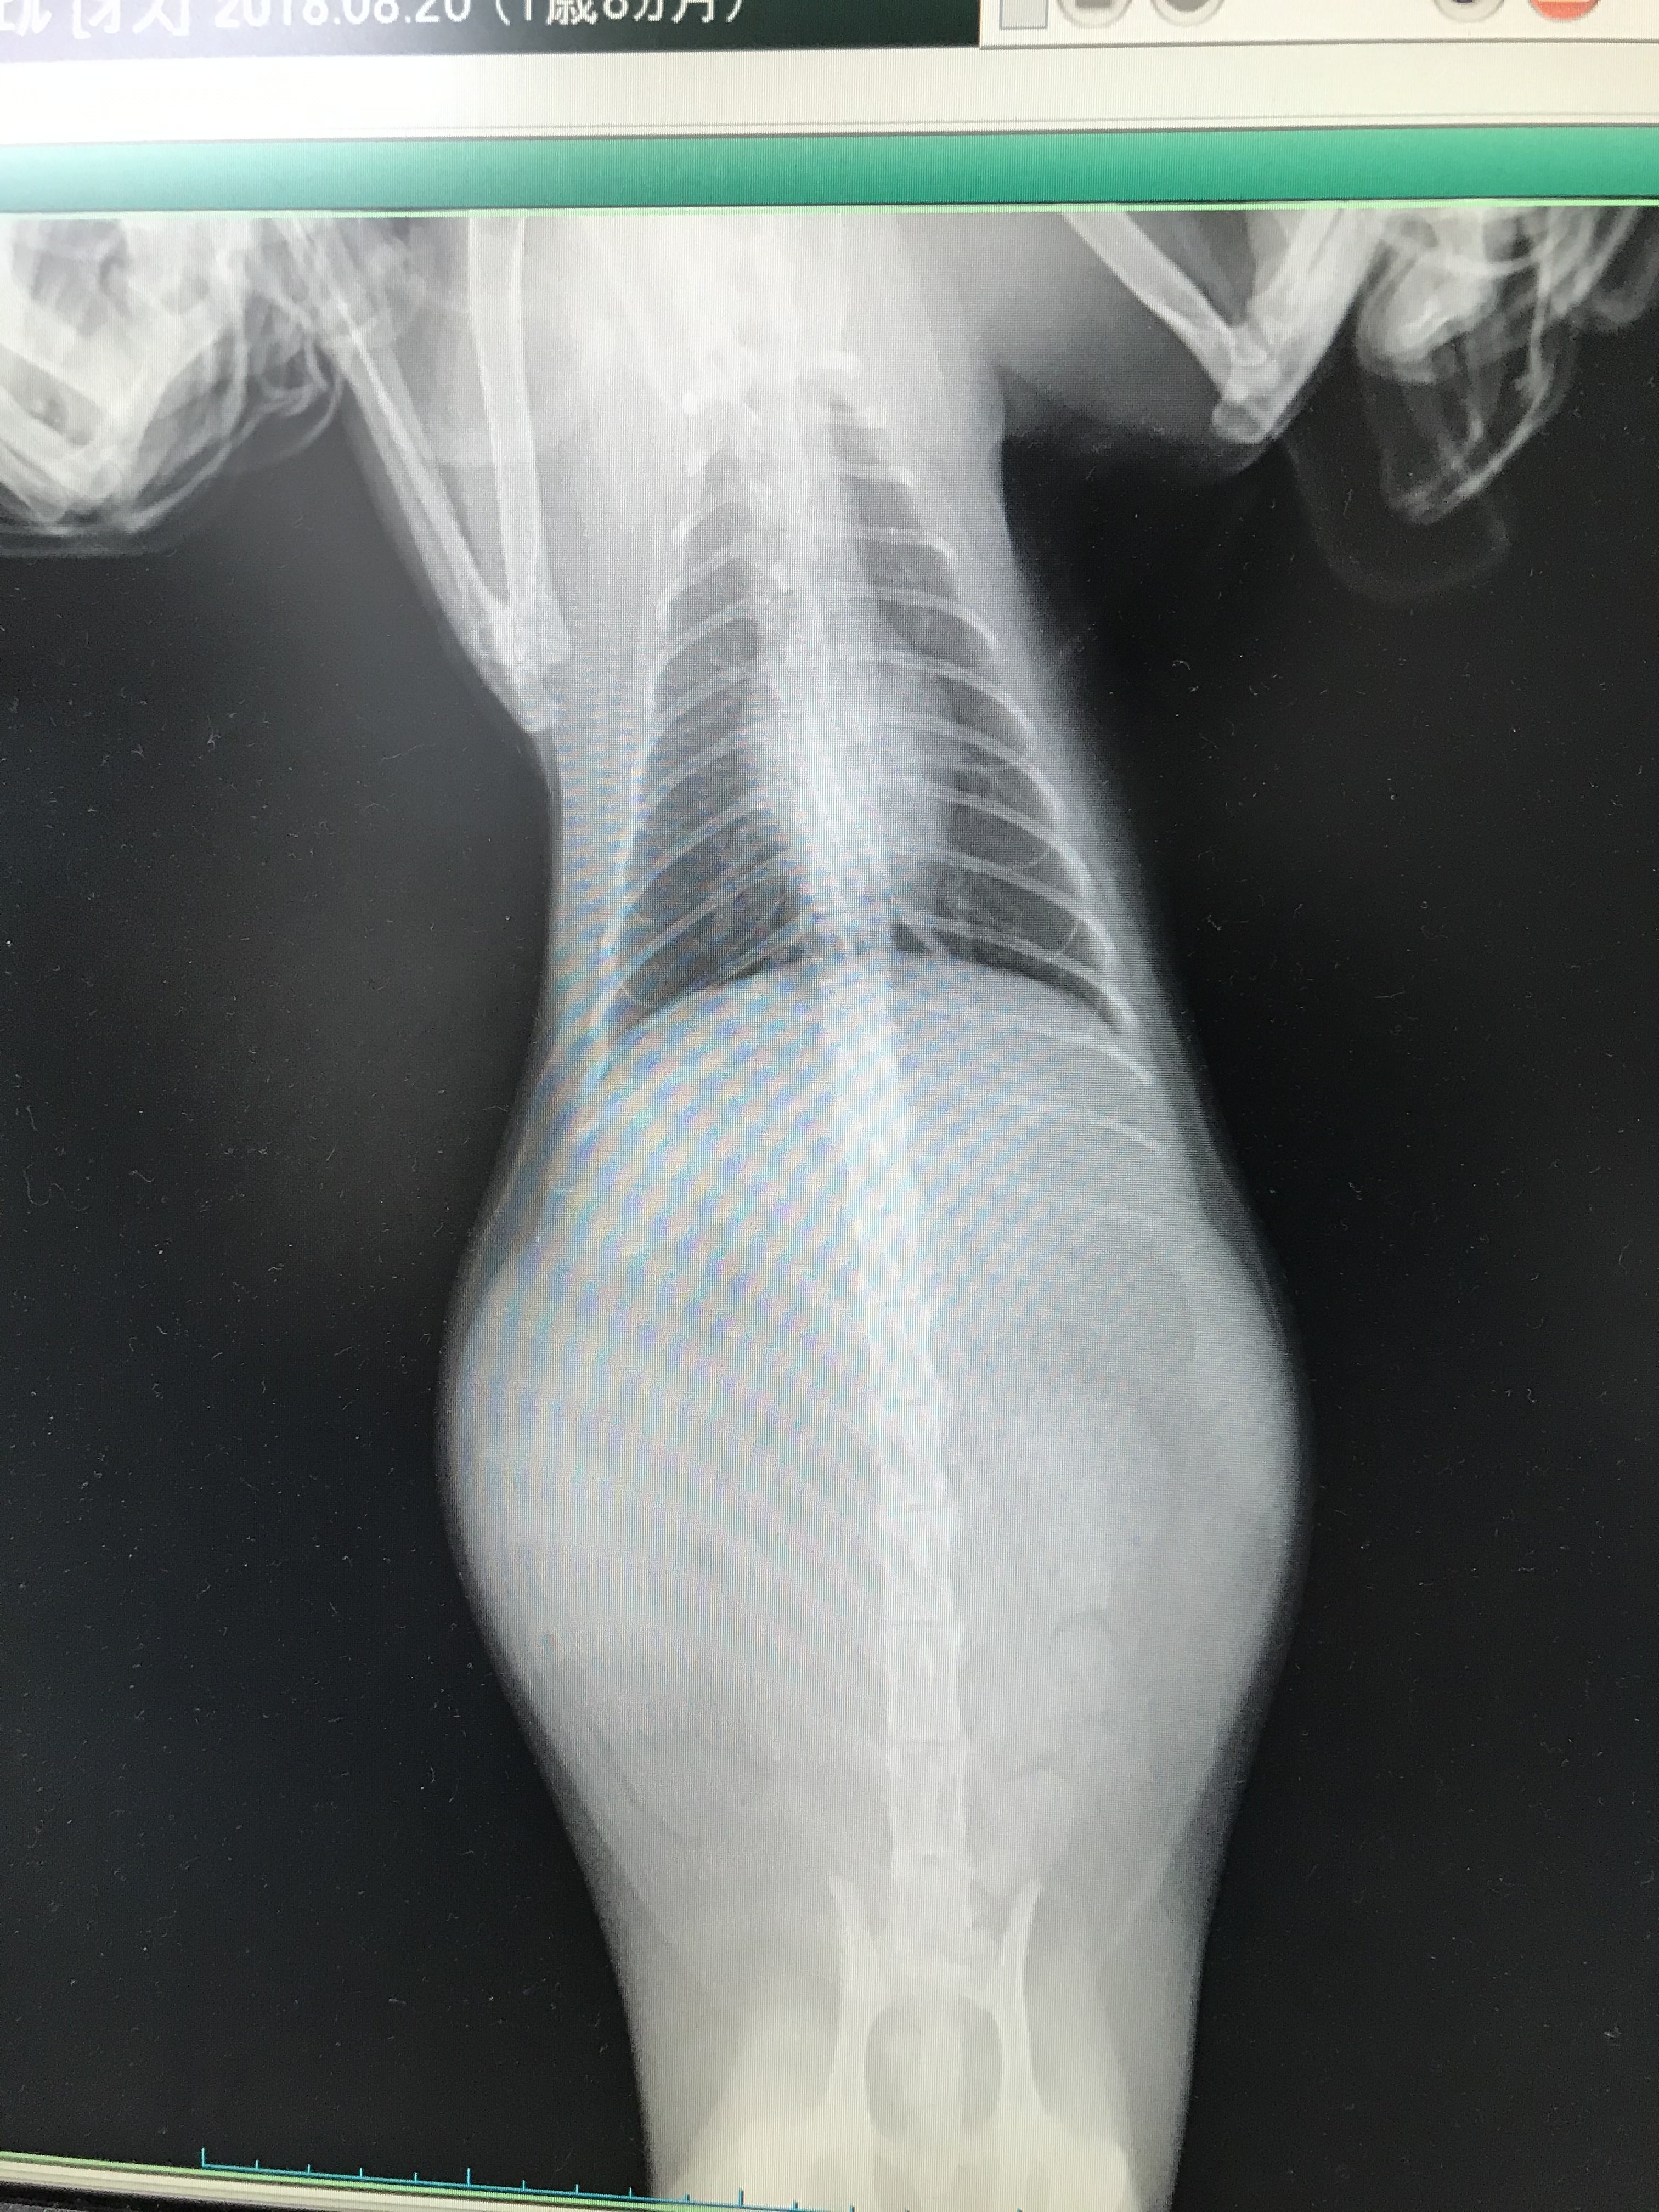

ミエルの場合一番初めに気づいた異変はお腹の張りと食欲不振でした。

腹水がたまり食欲もなくなり水を飲むことも減っていき一日寝たままで過ごし徐々に軽くなりあんなに重たくなったね、大きくなったね、と言っていた体も一回り小さくなり、日に日に背骨は浮き出て不安な毎日でした。

FIPの診断はとても難しくウェットタイプとドライタイプの現時点ではウェットタイプでした。